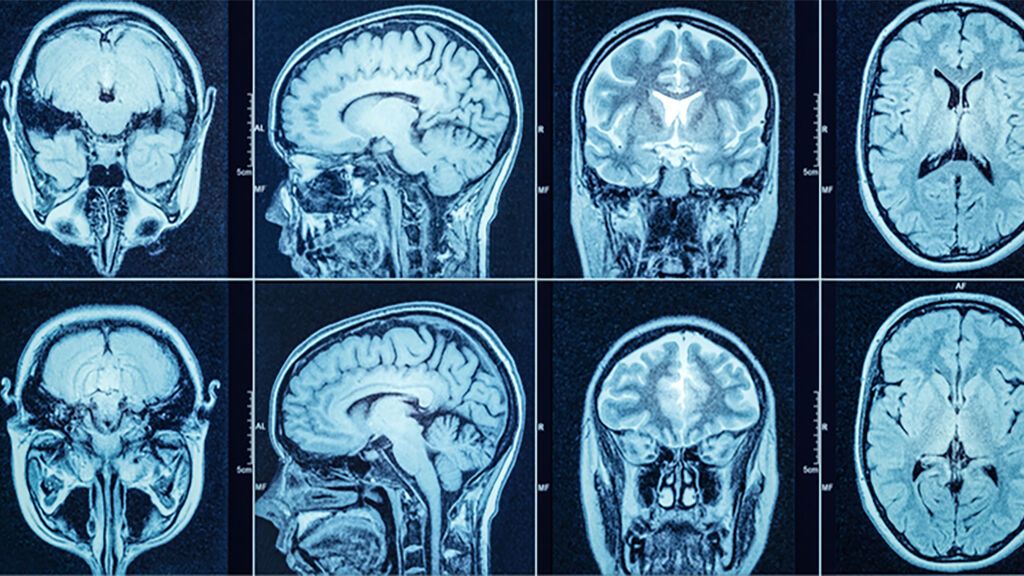

El glioblastoma es el tumor cerebral más frecuente y agresivo

Investigadores del Vall d'Hebron Instituto de Oncología (VHIO) han demostrado la eficacia preclínica de un nuevo fármaco inmunológico basado en un anticuerpo que es capaz de lograr la regresión del glioblastoma, el tumor cerebral más frecuente y agresivo.

La revista "Molecular Cancer Therapeutics" acaba de publicar los resultados del estudio preclínico de este fármaco, realizado tanto con modelos "in vitro" como en modelos "in vivo", utilizando muestras de pacientes de glioblastoma.